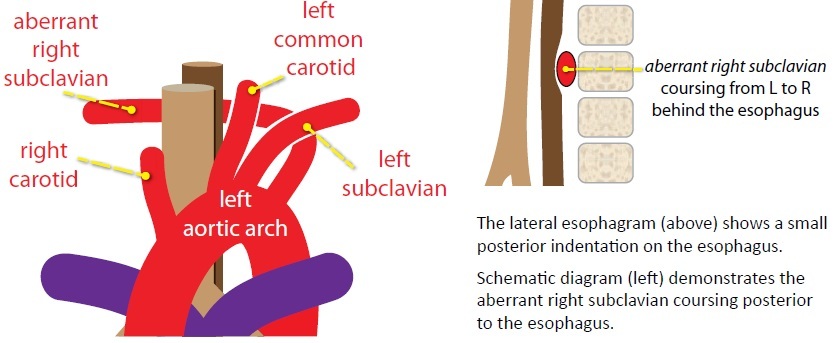

Rings and slings are important vascular causes of stridor in infancy and childhood. The typical initial evaluation is with barium esophagram, followed by CT or MRI if abnormal.

Complete encircling of the trachea and esophagus by the aortic arch or great vessels is a vascular ring.

The three most important vascular causes of stridor are double aortic arch, right arch with aberrant left subclavian artery, and pulmonary sling. Each of these will show abnormality on the lateral radiograph or esophagram.

The double aortic arch and right arch with aberrant left subclavian artery look the same on radiography/esophagram, each producing a posterior impression on the esophagus.

Right arch with aberrant left subclavian artery

The second most common vascular ring is a right aortic arch with an aberrant left subclavian artery. The right arch indents the anterior trachea while the aberrant left subclavian artery wraps posteriorly around the esophagus. The ring is completed by the ligamentum arteriosum.

In contrast, the mosre common anatomical variant of a left arch with an aberrant right subclavian artery is a (usually) asymptomatic normal variant that is not a vascular ring.

On the frontal view, a right arch with aberrant left subclavian artery produces a leftward impression/deviation of the tracea by the right aortic arch.

Left aortic arch with aberrant right subclavian artery

A left aortic arch with an aberrant right subclavian artery is not a ring or a sling, and is not a cause of stridor. It almost never causes symptoms, but in the rare case that is does, dysphagia may result, which is called dysphagia lusoria.